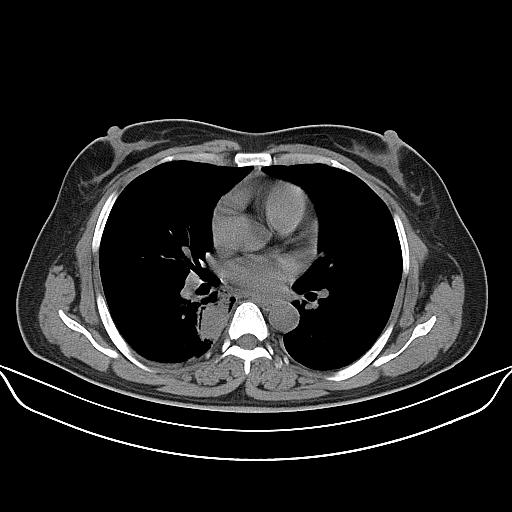

标题: CT22224:肺部肿块

f,48,主因咳嗽咳血来我院检查,无发热。

右肺癌肿

病灶边缘尚清,主体位于后下总膈,不除外神经源性肿瘤,建议行mri检查。

1)右肺下叶背段团块状软组织密度影;建议抗炎治疗后复查排除肿瘤性病变。2)右侧少量胸腔积液。